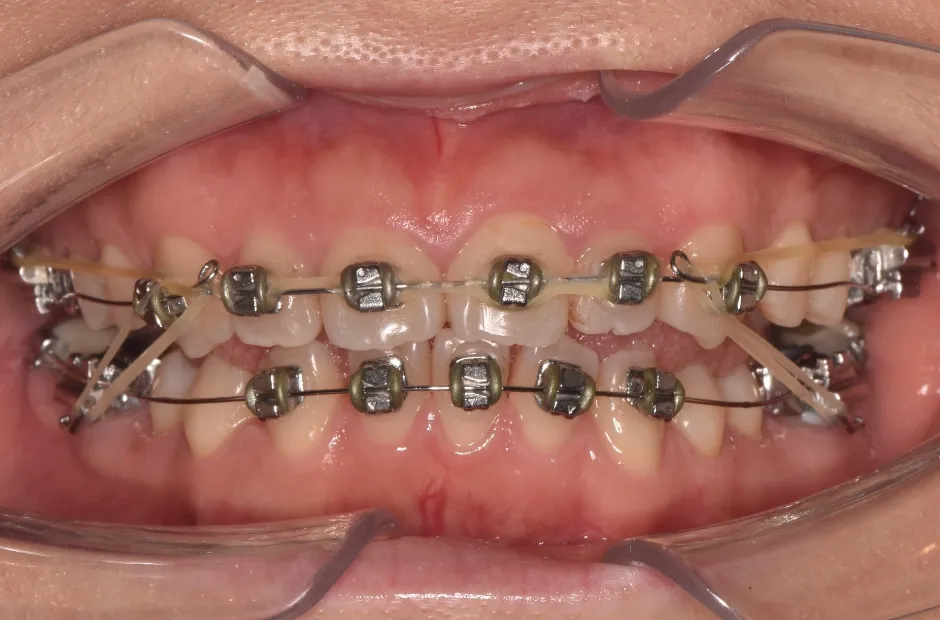

| 診断名・主訴 | 下顎前突、叢生 |

|---|---|

| 年齢・性別 | 23歳・女性 |

| 治療期間・回数 | 3年 |

| 治療に用いた主な装置 | 上顎5,5 下顎4,4 |

| 抜歯部位 | 舌側矯正 |

| 治療費 | 100万円(税抜) |

| リスク・副作用 | 装置による違和感・疼痛・歯肉退縮・歯根吸収・虫歯のリスクなど |

治療中